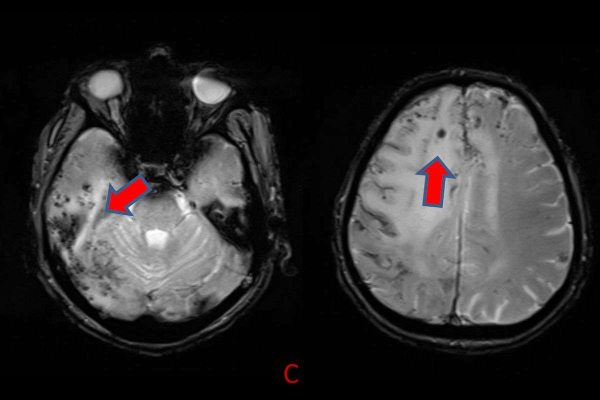

- C) Gradient seride milimetrik hemosiderin kalıntıları ve süperfisyal siderozis (kırmızı ok)